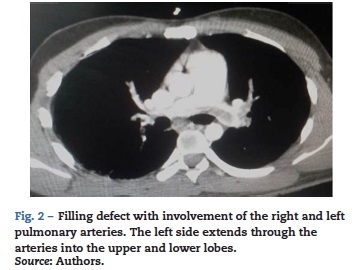

The patient was transferred to Intensive Care with invasive ventilation support and noradrenalin infusion at 0.1 mcg/k/min and vasopressin at 0.01 x/min. A chest CT angiography was positive for massive pulmonary thromboembolism involving both lower lobes and the left upper lobe associated with signs of severe pulmonary hypertension (Fig. 2).